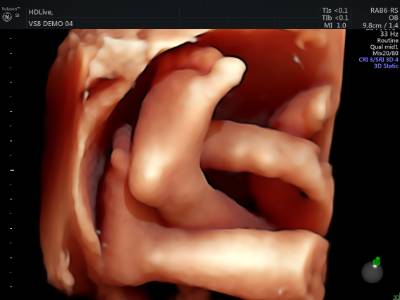

Hoy en día, la ecografía 3D y 4D permiten ver la morfología del feto y su reconstrucción en tres dimensiones. Con la aplicación en 4D es posible además contemplar al feto en movimiento, interpretando también su relación con el medio.

Desde el punto de vista afectivo, la obtención de imágenes de gran calidad y realismo, que suelen ser más fáciles de interpretar para los padres, proporciona indudables ventajas de tipo psicológico, mejora la relación de la madre con el feto y la gestión de los síntomas provocados por el embarazo.